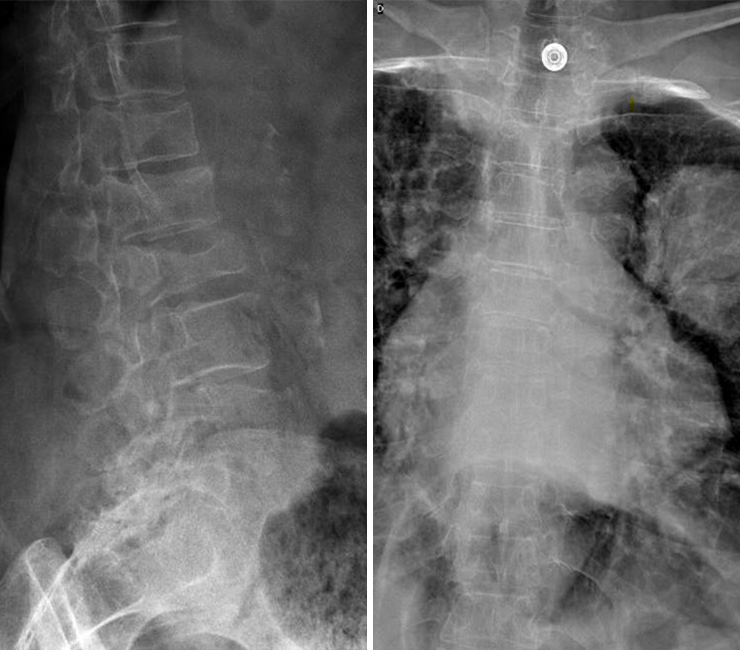

Vous faites réaliser une radiographie du rachis dorso-lombaire dont voici les clichés. Figure 1 (Salomé Abdellaoui, La Revue du Praticien)

Question 4 - Qu’identifiez-vous sur cette radiographie (une ou plusieurs réponses exactes) ?

Il existe bien une image pulmonaire suspecte mais elle est située dans le poumon gauche (légendée par une étoile).

Il s’agit d’une électrode d’électrocardiogramme.

On observe sur les radiographies une fracture vertébrale de L2, qui n'a pas de caractère évident de malignité (voir la suite du dossier), ainsi que des fractures plateaux supérieurs des vertèbres T12 et L1. Figure 2 (Salomé Abdellaoui, La Revue du Praticien)

Devant la présence d’une image pulmonaire gauche suspecte, vous craignez que la fracture vertébrale identifiée en L2 soit d’origine néoplasique.